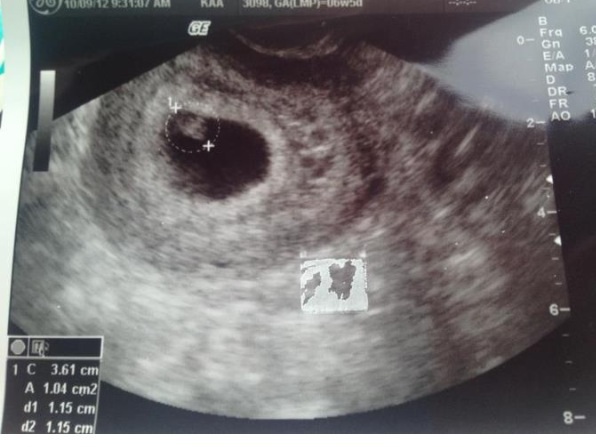

I am just sick and bored and wondering if anyone knows how that theory works with my 7 week scan lol Attachment 5502

It was a vaginal u/s btw